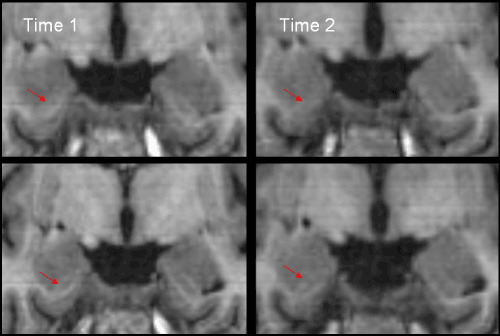

| Figure 3: HC head can begin anterior to the IHLV. The red arrows indicate the alveus (which separates the HC from the amygdala (AG)). Top images are 7mm posterior to the anterior commissure, bottom images are 8mm posterior to the anterior commissure. |